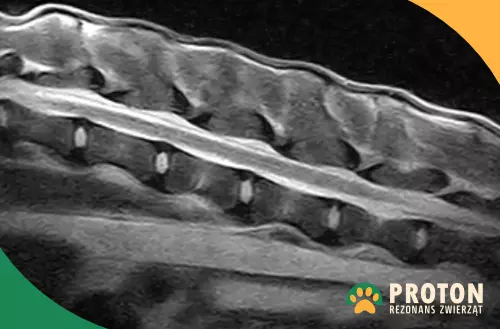

W trakcie badania lekarz ocenia struktury kostne (trzony i łuki kręgów, wyrostki), krążki międzykręgowe, więzadła oraz struktury nerwowe (rdzeń kręgowy wraz z wychodzącymi korzeniami nerwowymi). W badaniu RM widoczne jest ponadto umięśnienie okolicy kręgosłupa.

Lekarz analizuje kolejne przekroje kręgosłupa w kilku płaszczyznach, poszukując nieprawidłowych zmian, które mogą być odpowiedzialne za obecność objawów obserwowanych u zwierzaka.

Rezonans kręgosłupa psa - rdzeń kręgowy